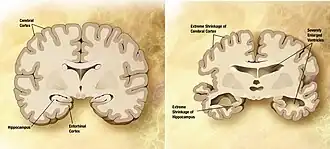

![]() Мозг пожилого человека в норме (слева) и при патологии, вызванной болезнью Альцгеймера (справа), с указанием отличий. | |

Болезнь характеризуется потерей нейронов и синаптических связей в коре головного мозга и определённых субкортикальных областях. Гибель клеток приводит к выраженной атрофии поражённых участков, в том числе к дегенерации височных и теменной долей, участков фронтальной коры и поясной извилины[67].